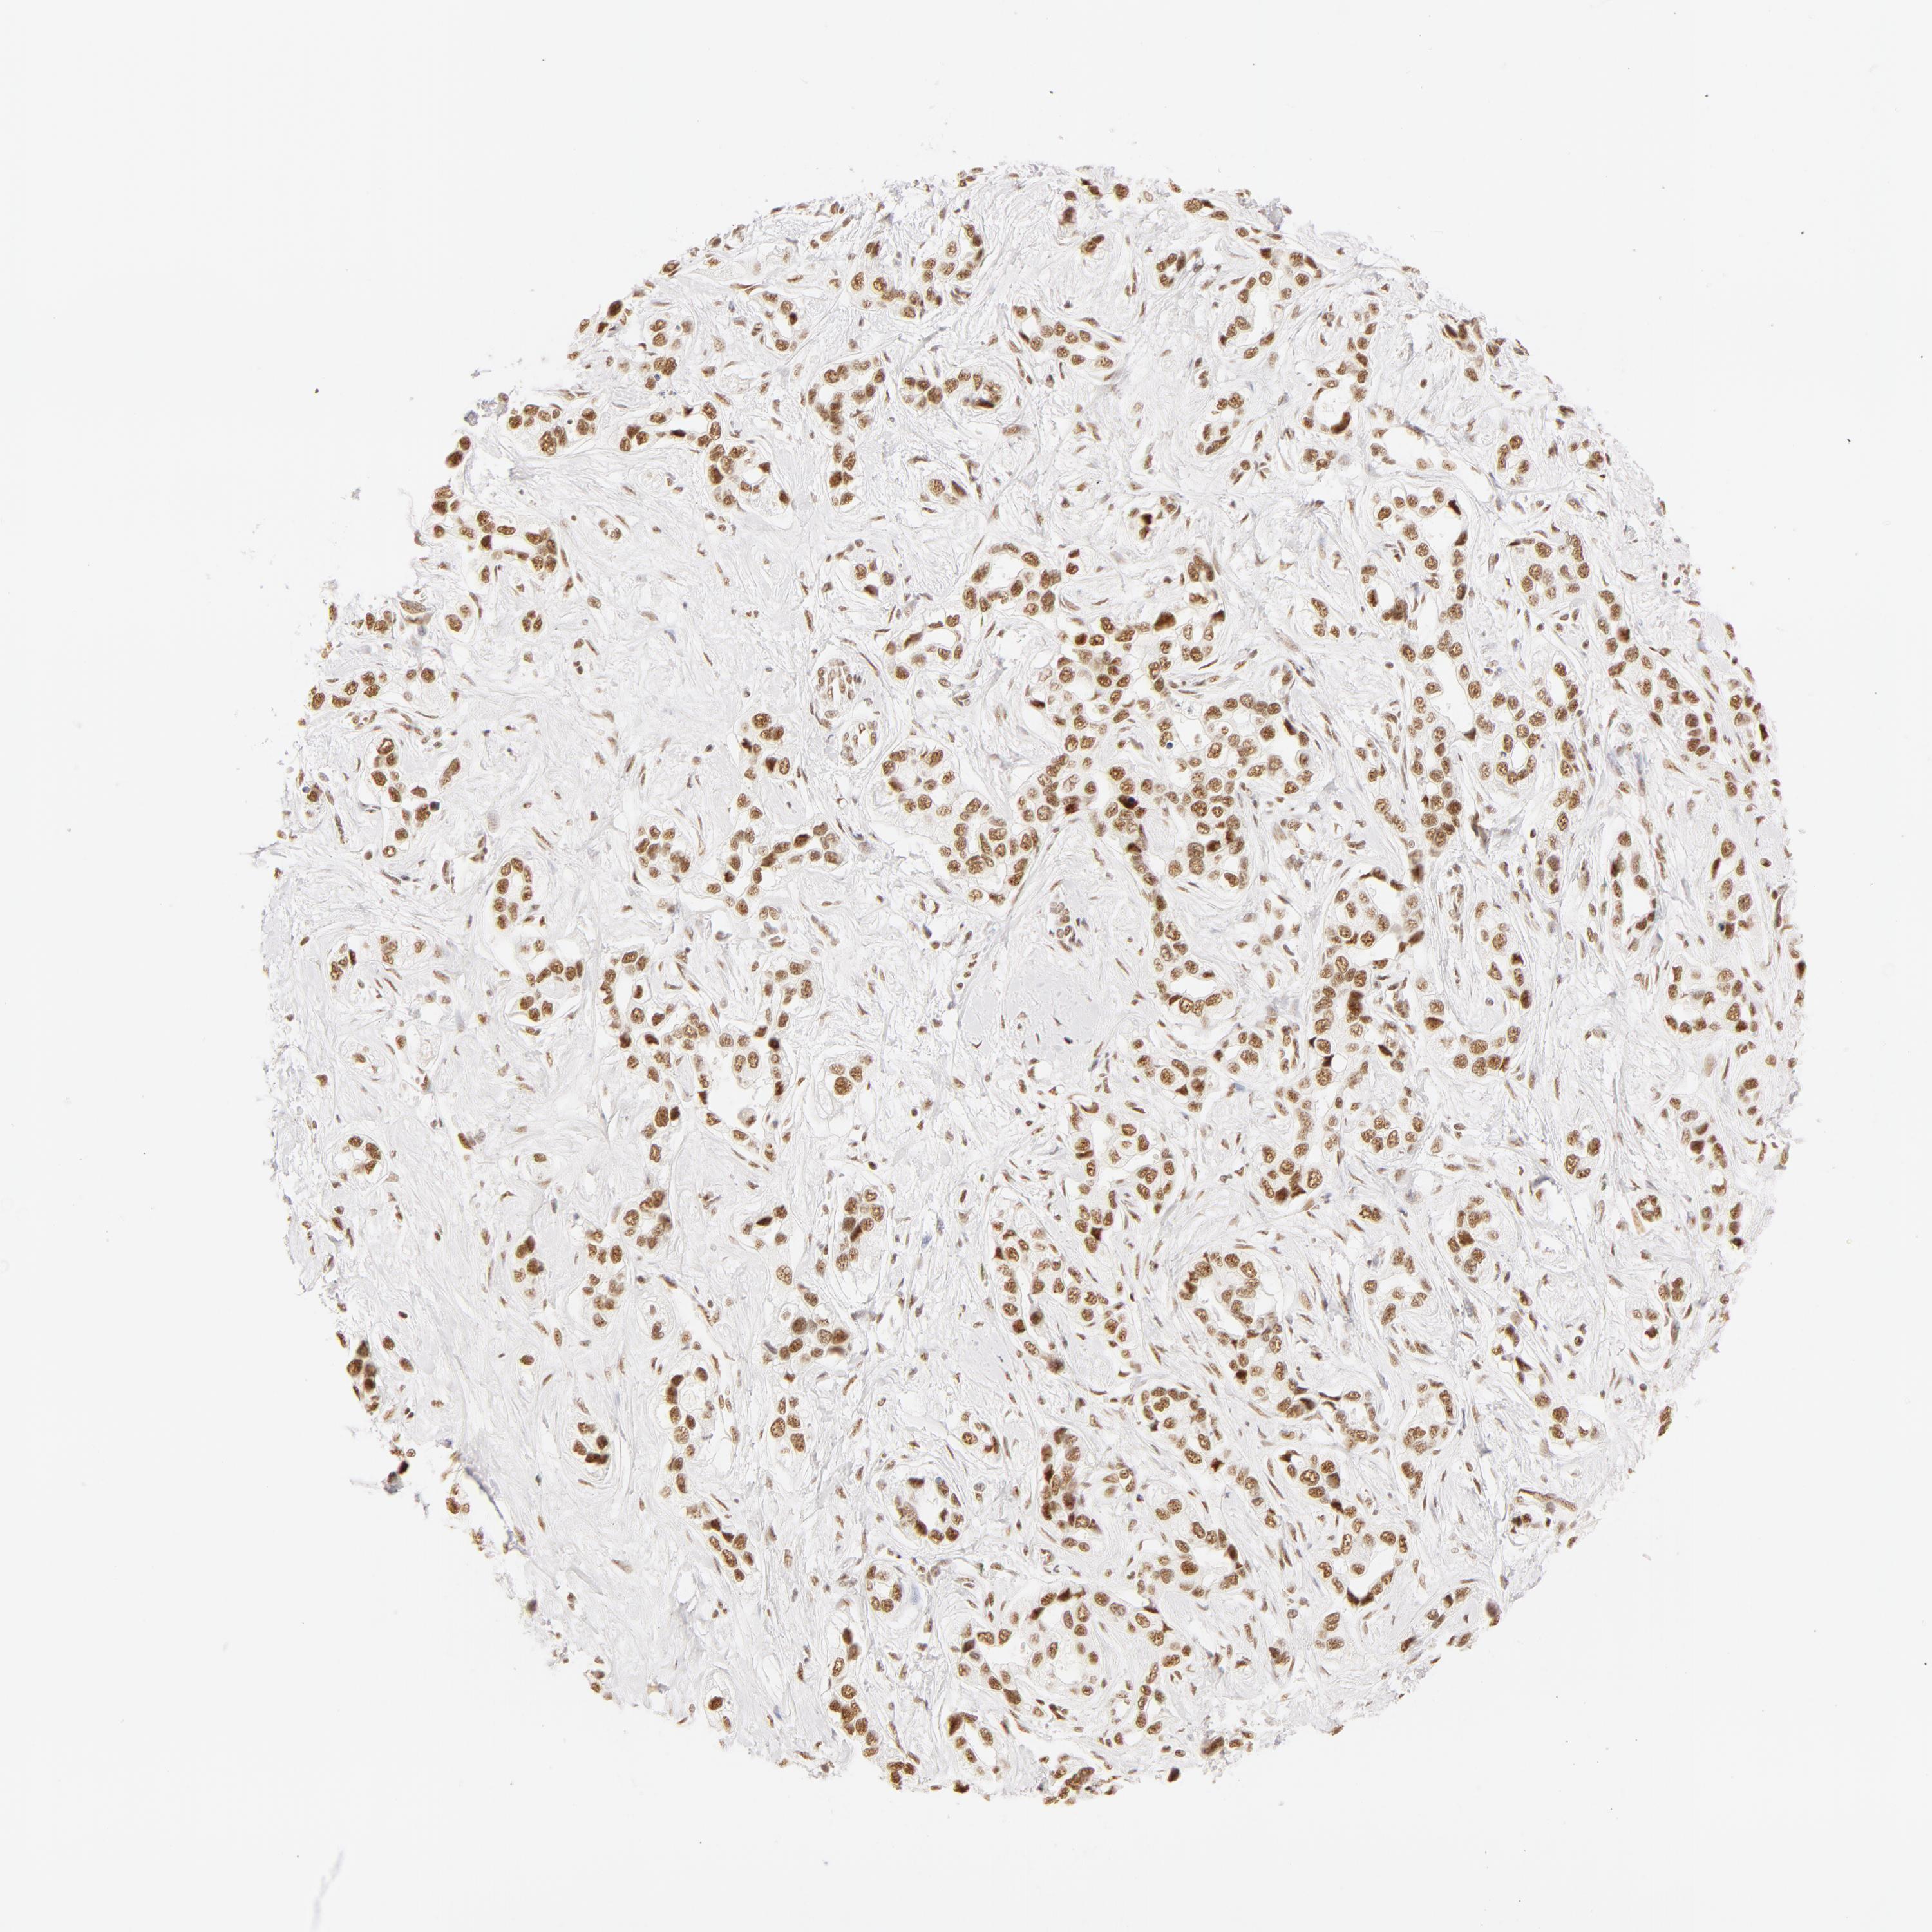

LIVER CANCER - Protein expressioni

A mouse-over function shows sample information and annotation data. Click on an image to view it in a full screen mode. Samples can be filtered based on level of antibody staining by selecting one or several of the following categories: high, medium, low and not detected. The assay and annotation is described here.

Note that samples used for immunohistochemistry by the Human Protein Atlas do not correspond to samples in the TCGA dataset.

Antibody stainingi

Antibody staining in the annotated cell types in the current human tissue is reported as not detected, low, medium, or high, based on conventional immunohistochemistry profiling in selected tissues. This score is based on the combination of the staining intensity and fraction of stained cells.

Each image is clickable and will lead to virtual microscopy that enables deeper exploration of all samples and also displays staining intensity scores, fraction scores and subcellular localization as well as patient and tissue information for each sample.

Antibody HPA001591

Staining

High

Medium

Low

Not detected

Intensity

Strong

Moderate

Weak

Negative

Quantity

>75%

75%-25%

<25%

None

Location

Nuclear

Cytoplasmic/membranous

Cytoplasmic/membranous,nuclear

Carcinoma, Hepatocellular, NOS